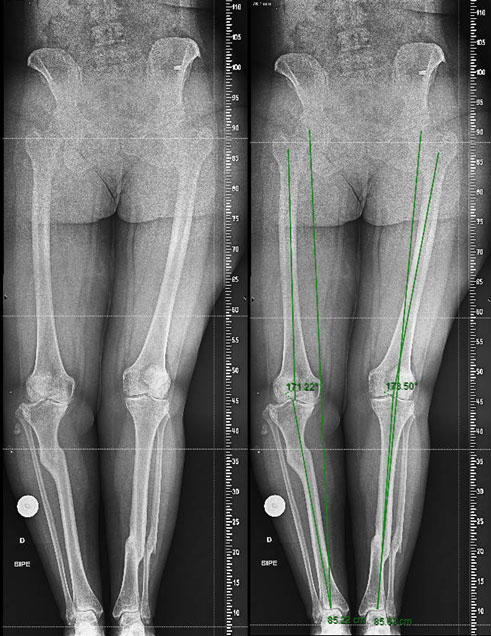

Management of a post-traumatic knee pain: Pre-op XRays

Pre-op XRays

• Double varus deformity (tibial and intraarticular) ✔️

• MPTA < 85°1,2 ✔️

• HKA <175°1,2 ✔️